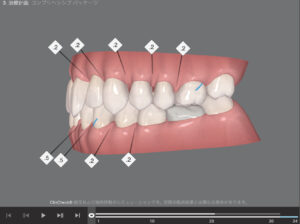

🔶アフター🔶

右